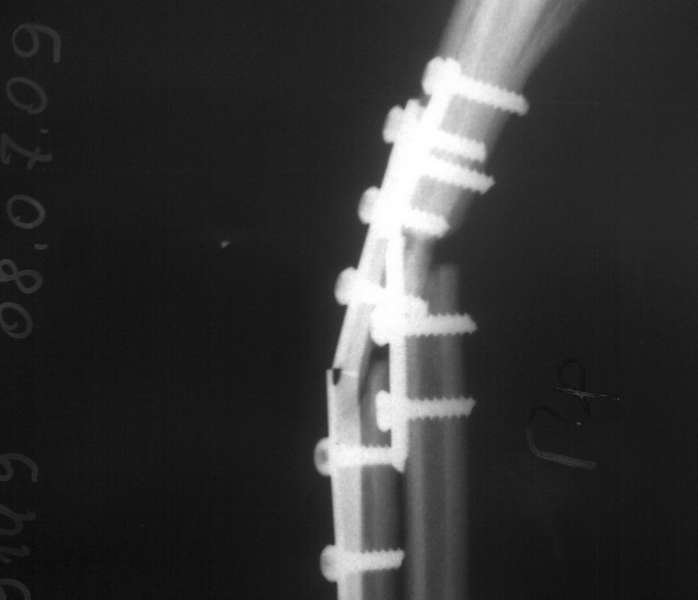

Пациентка С. 23 лет. В марте 2009 года операция остеосинтез костей предплечья пластинами по поводу оскольчатого перелома.

04.07.09. при совершении супинационных движений предплечья ощутила хруст (низкоэнергетическая травма). На рентгенограммах несросшийся перелом костей предплечья, перелом конструкций. Коллеги подскажите что делать, поделитесь опытом.